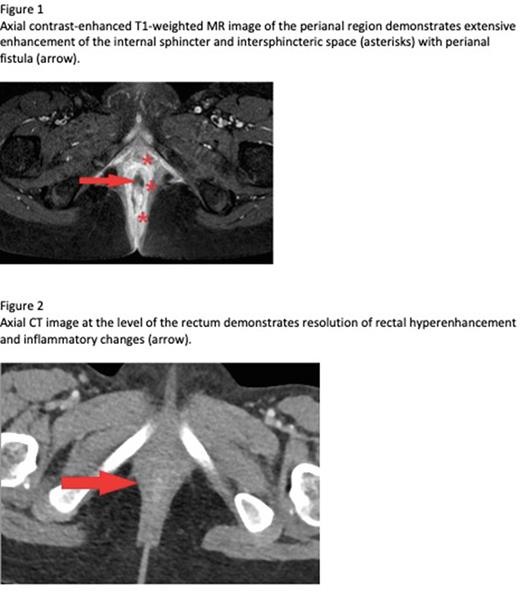

Case: A 7yoF presented with fever and pancytopenia in the setting of Human Metapneumovirus and Parainfluenza. Bone marrow biopsy showed hypocellularity (60-70%) with granulocytic and megakaryocytic hypoplasia, favoring viral suppression. Ultimately, she progressed to transfusion dependence. Repeat bone marrow aspirate and biopsy ultimately revealed bone marrow aplasia, DEB chromosomes, telomere lengths, and PNH clones were negative, confirming the diagnosis of vsAA. She was subsequently admitted for febrile neutropenia (F&N) and was found to have mild respiratory COVID-19, but began to complain of rectal pain that was initially attributed to her history of constipation. She defervesced on IV antibiotics (abx) and was discharged home with negative cultures. Within a week she represented with hematochezia and F&N and was found to have proctitis with perianal fistula on MRI (figure 1); GI PCR panel was + Enteroaggregative E. coli, no resistant organisms were identified. She clinically improved and discharged on IV piperacillin-tazobactam (pip-tazo). Despite 2 weeks of IV abx, she developed new fever and imaging confirmed persistent proctitis with peri-rectal abscess. As she had limited response to abx alone we trialed a short course of granulocytes with improvement in anorectal inflammation by CT. She was discharged with a plan to continue IV pip-tazo until achieving radiographic cure; however, interval imaging after an additional 2 weeks of abx showed rebound of her proctitis and she was again admitted with F&N and rising inflammatory markers. Her failure to eradicate her peri-rectal infection despite prolonged antibiotics (>4weeks), along with her previous response to a short course of granulocyte transfusion prompted us to prescribe a prolonged 10-day course of granulocytes with continued antibiosis. Her post-granulocyte CT showed resolution of her perirectal abscess and proctitis (figure 2). With resolution of her infection, she was able to proceed to HSCT which she completed without recurrence of her anorectal infection.